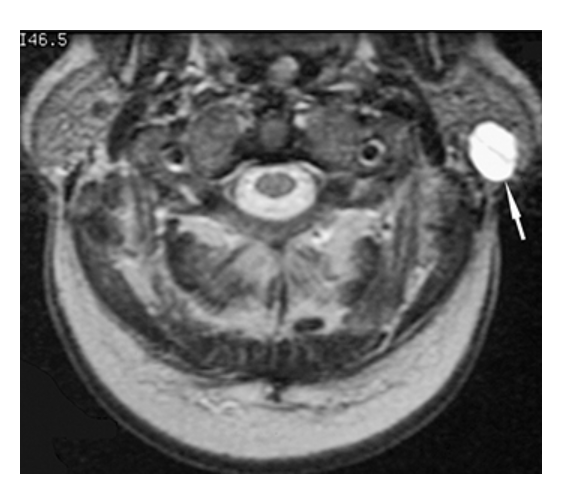

What does the figure show?

Parotid Gland Tumor. T1-weighted axial MRI of the parotid gland demonstrates a well-defined, round, low-signal intensity mass (arrow) in the posterior aspect of the superficial lobe of the left parotid gland.

Parotid Gland Mass. T2-weighted axial MRI of the parotid gland demonstrates a well-defined high-signal intensity mass (arrow) of the posterior aspect of the superficial lobe of the left parotid gland consistent with a pleomorphic adenoma.